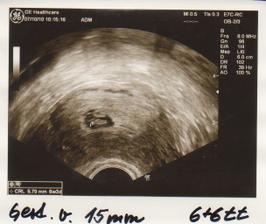

Taááákže 2. KET při 3. IVF